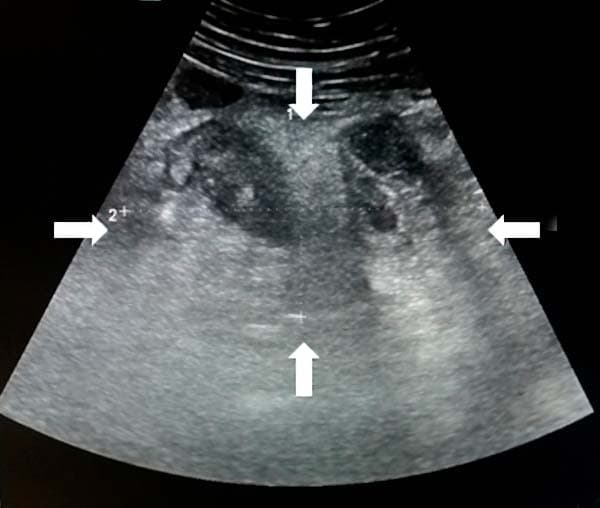

Аппендикулярный инфильтрат — это конгломерат спаянных между собой органов, располагающихся вокруг воспаленного червеобразного отростка, отграничивающих его от свободной брюшной полости (см. рис. 16). Аппендикулярный инфильтрат возникает у 3–5 % больных, как правило, спустя 4–5 суток от начала острого аппендицита. Аппендикулярный абсцесс возникает вследствие нагноения инфильтрата, перфорации аппендикса.

Рисунок 16. Инфильтрат в правой подвздошной области.

Из протокола УЗИ: «В правой подвздошной области визуализируется инфильтрат, определяется свободная жидкость межпетельно» (см. рис. 17).

Рисунок 17. УЗ-визуализация инфильтрата.